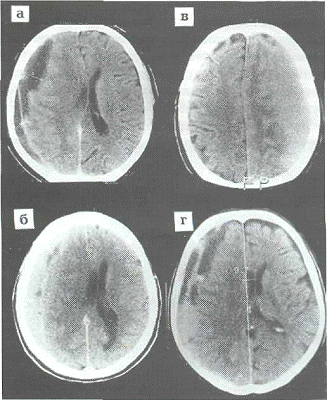

Описанные компьютерно-томографические

признаки односторонних ХСГ во многом характерны и для двухсторонних ХСГ. Однако

необходимо отметить некоторые особенности их воздействия, которые весьма

существенны для диагностики изоденсивных двухсторонних ХСГ, а также в тех

случаях, когда лишь одна из гематом имеет одинаковую с мозгом плотность. На

нашем материале подтверждается так называемый феномен "заячьих ушей",

который заключается в более или менее равномерном сдавлении обоих боковых

желудочков и сближении их передних рогов. При этом одновременно изменяется

контур талии боковых желудочков, а при ХСГ, занимающих оба полушария целиком,

одновременно может наблюдаться и сближение задних рогов (рис.9).

Важным и легко доступным признаком для

обнаружения именно билатеральных ХСГ является отсутствие субарахноидальных

щелей с обеих сторон (рис.9). Этот факт особенно значим улиц пожилого и

старческого возраста, у которых, как правило, субарахноидальные щели в

противоположном полушарии при односторонней ХСГ расширены.

Рис.9. Кт при двухсторонней ХСГ. Сближение

передних и задних рогов боковых желудочков, сужение их талии; отсутствие

конвекситальных субарахноидальных щелей с обоих сторон.